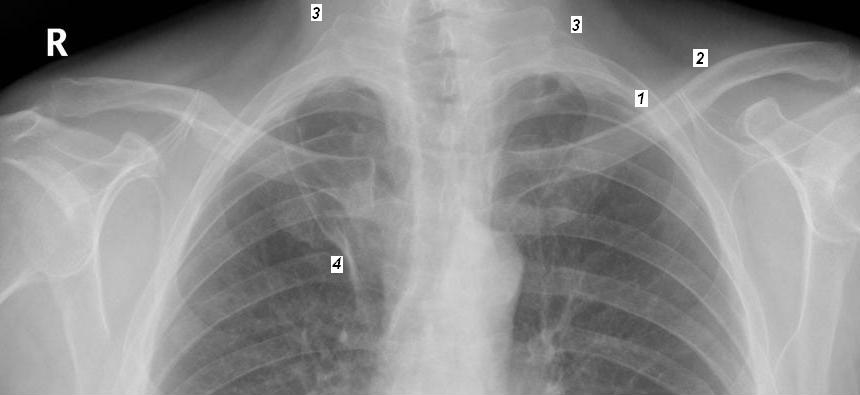

| Les images ce qui peut en pieges du cliche

de face : -1 Ombre accompagnement de la 2e

cote

-2 Ombre accompagnement de la clavicule

-3 Ombre de muscle sterno cleido-mastoidien

-4 Scissure azygos

-5 Parties molles du creux axillaire .

-6 Ombre de artere sous claviere

-7 Mamelon des hommes

- 8 Ombre des deux seins.

-9 Ombre des omoplates

-10 Calcification chondrosternales |

Arch posterieure des côtes sont bien

visible que arch anterieure , peu horizontal dans inspiration

profond et incline vers a bas dans expiration .

L'aspect du thorax peut change , normalement en trapeze , en

tonneau sur les asthms ou BPCO , pectus excavatum sur les

paralyse . Le cote peut atrophie , bifidite ou flottant (

C12 ) ..